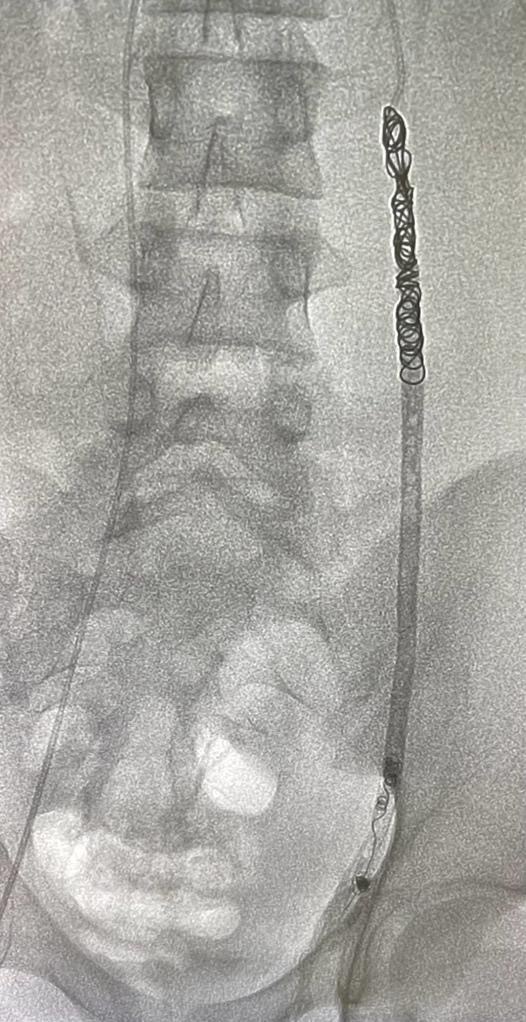

Varicocoeles?

A varicocele is an enlargement of the veins within the loose bag of skin that holds your testicles (scrotum). It’s similar to a varicose vein you might see on your leg. Varicoceles are a common cause of low sperm production and decreased sperm quality, which can cause infertility.